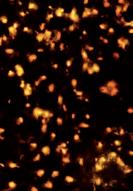

Zdjęcie mikroskopowe "Czy gwiazdy świecą na czerwono?"

przedstawia naturalną śmierć (samobójstwo) komórek raka szyjki macicy Zdjęcie wykonano w Dr Rath Research Institute

„Czy gwiazdy świecą na czerwono?“